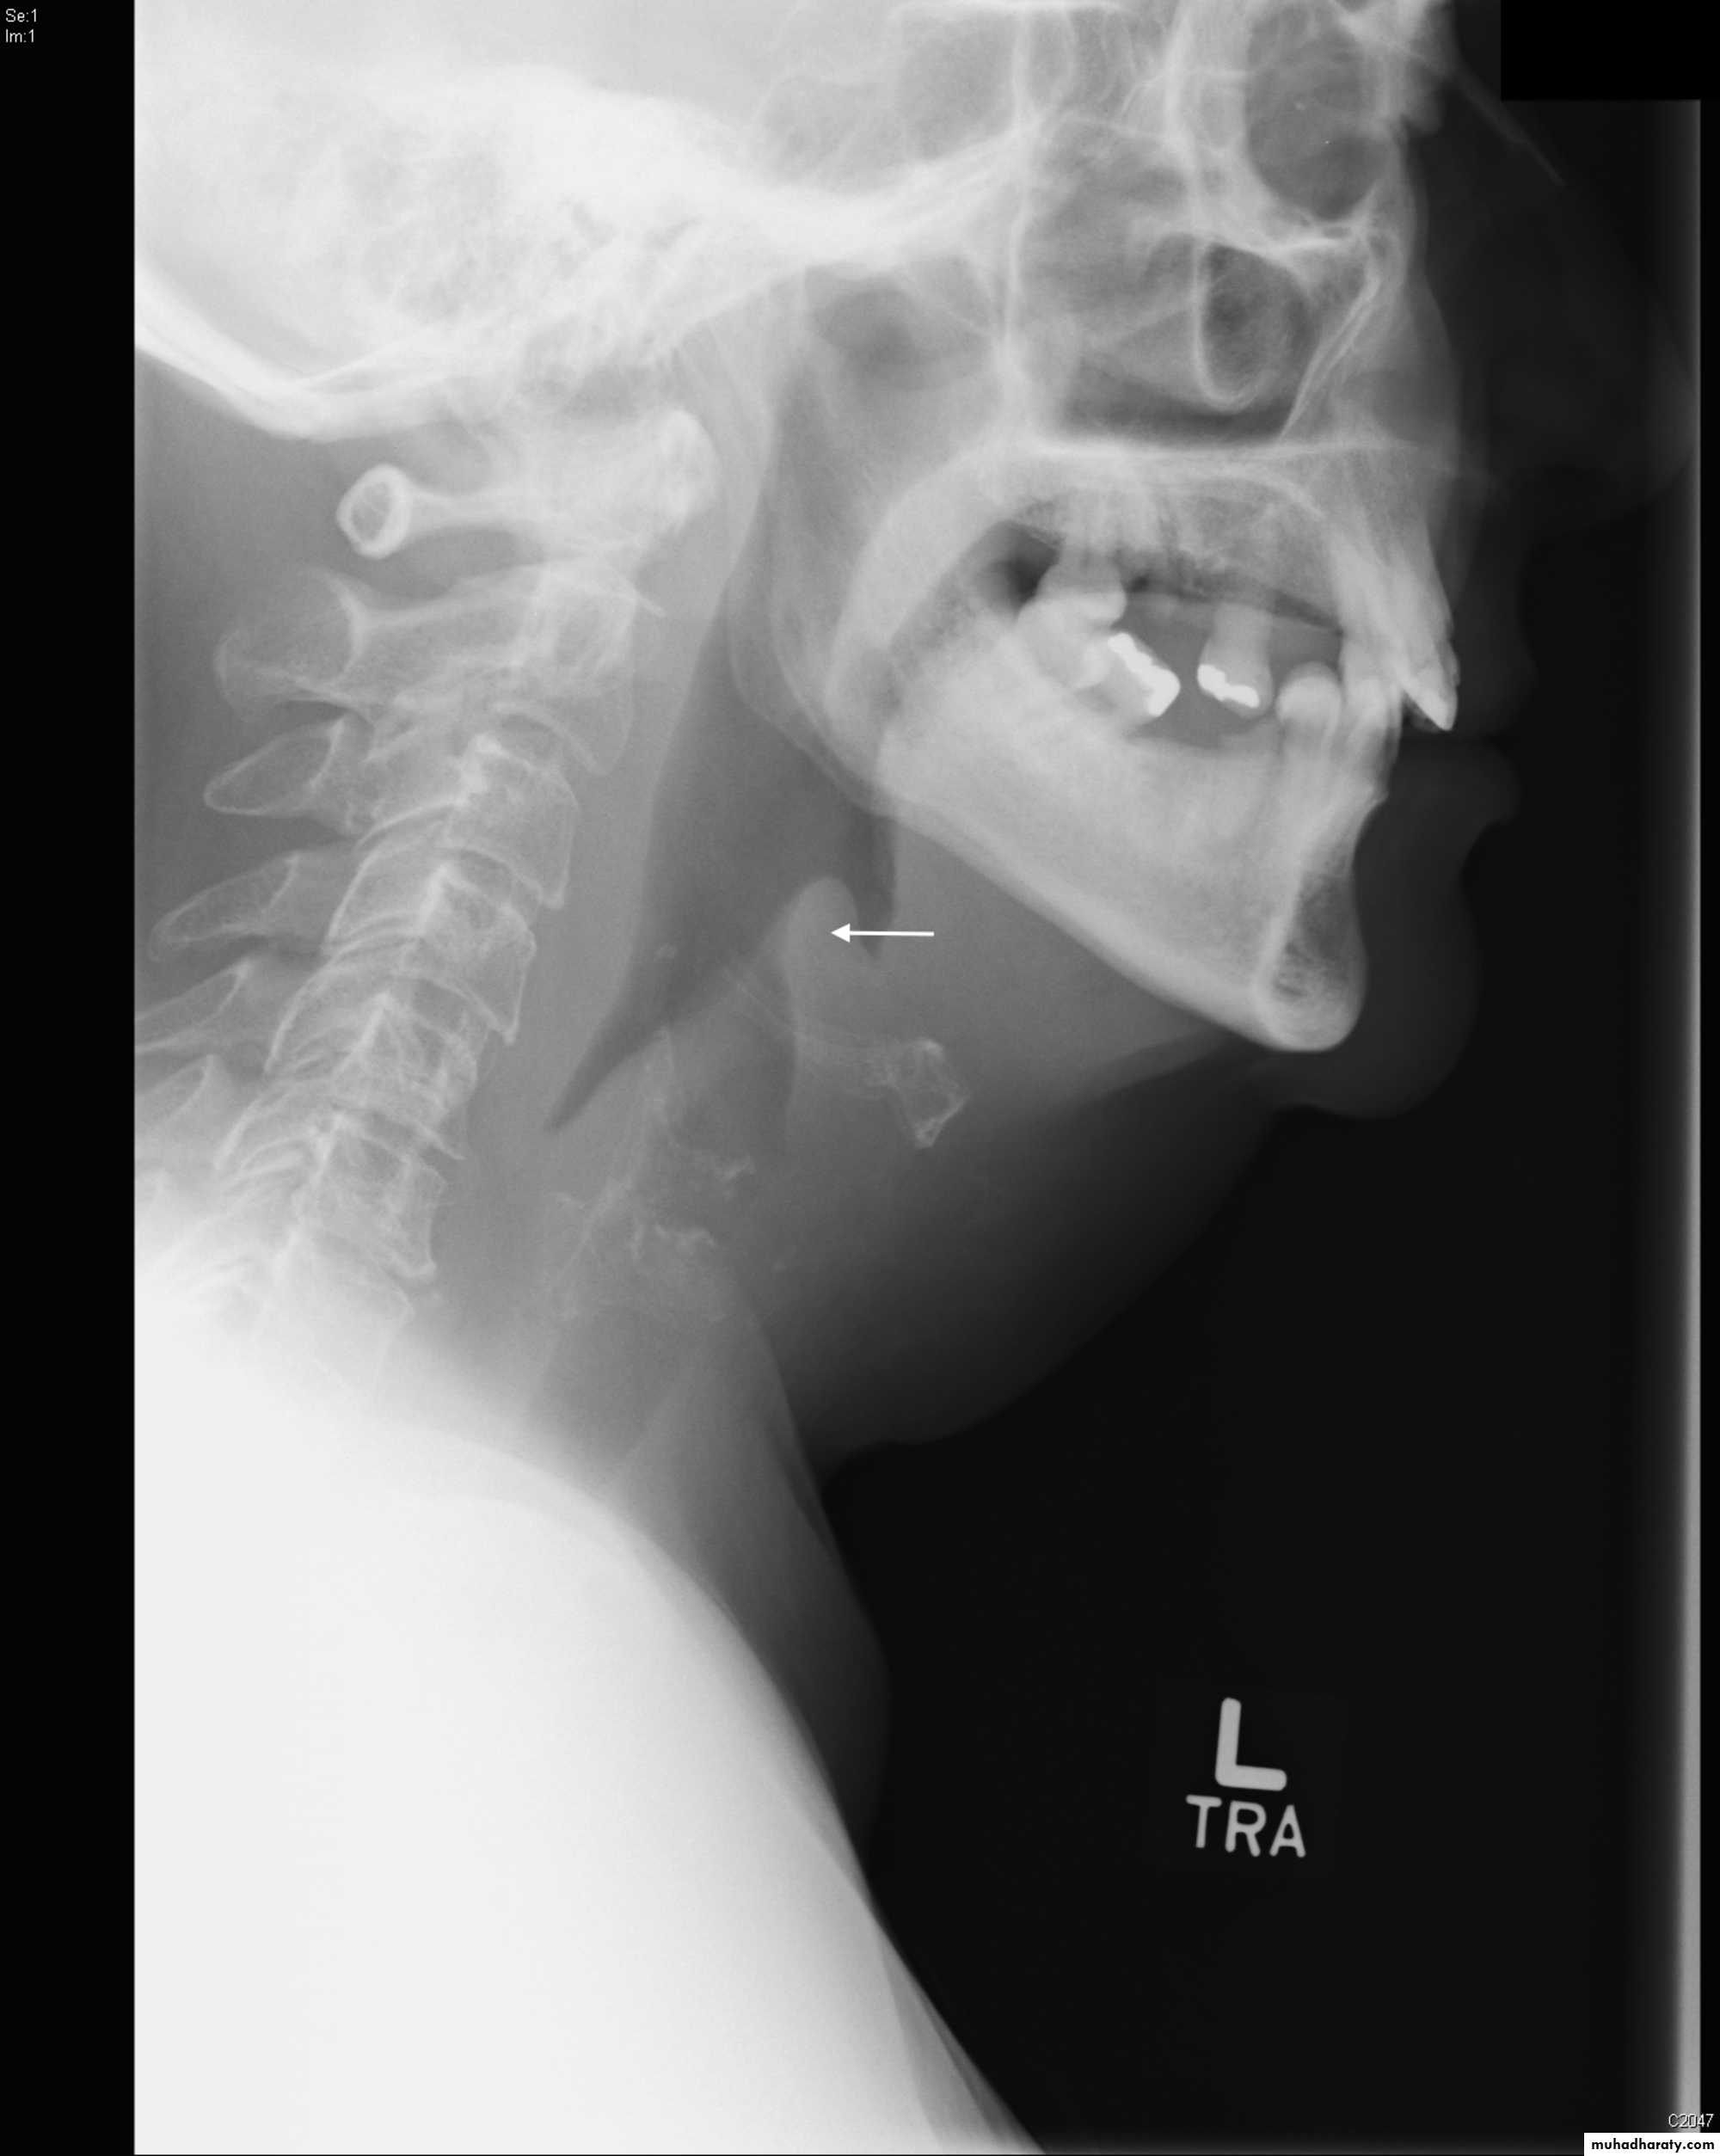

4 . X-ray of lateral neck give us thumb sign of swollen epiglottis .

X-ray in croup give us steeple sign due to narrowed subglottic space.